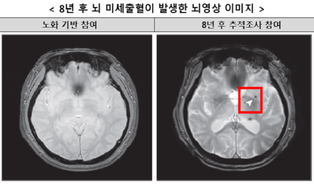

코로나19 백신과 암 발병 논란, 안전성 논의 필요

질병관리청이 13일 정례 브리핑에서 발표한 연구 결과가 오히려 논란을 불러일으키고 있다. 바로 코로나19 백신과 암 발생 사이의 인과성을 입증하기 어렵다는 내용이다. 그런데 이 설명이 백신 안전성에 대한 근본적인 의문을 해소하기보다는 ...